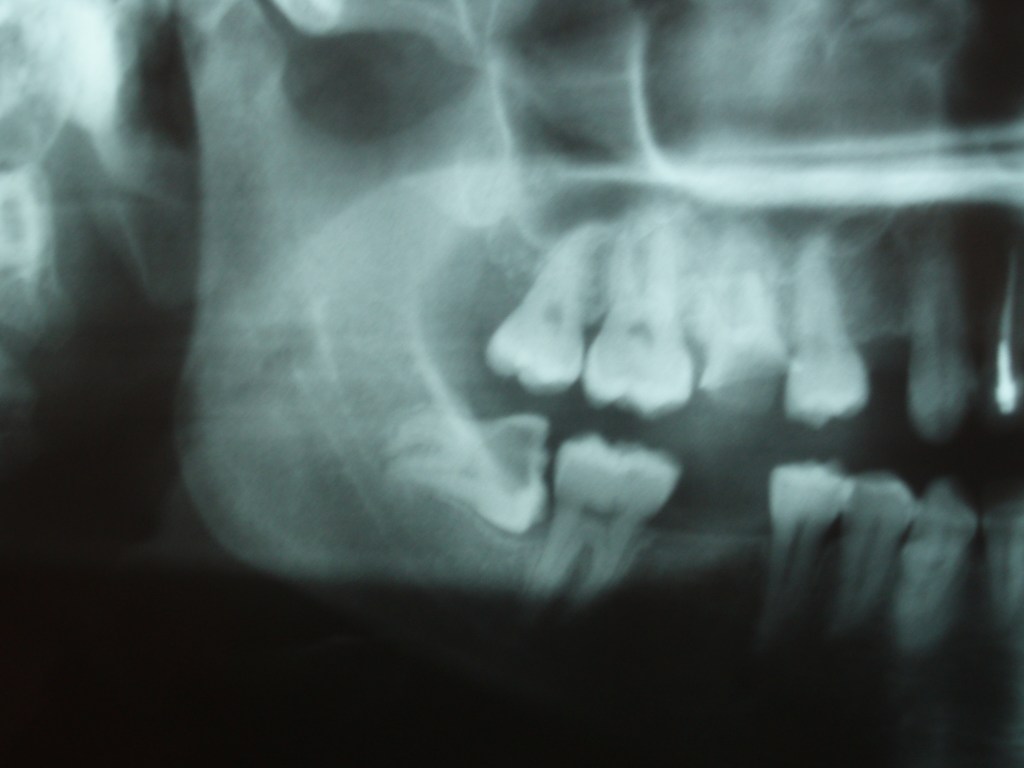

ΦΡΟΝΙΜΗΤΗΣ ΜΕ ΟΡΙΖΟΝΤΙΑ ΘΕΣΗ ΚΑΙ ΕΚΤΕΤΑΜΕΝΗ ΤΕΡΗΔΟΝΑ